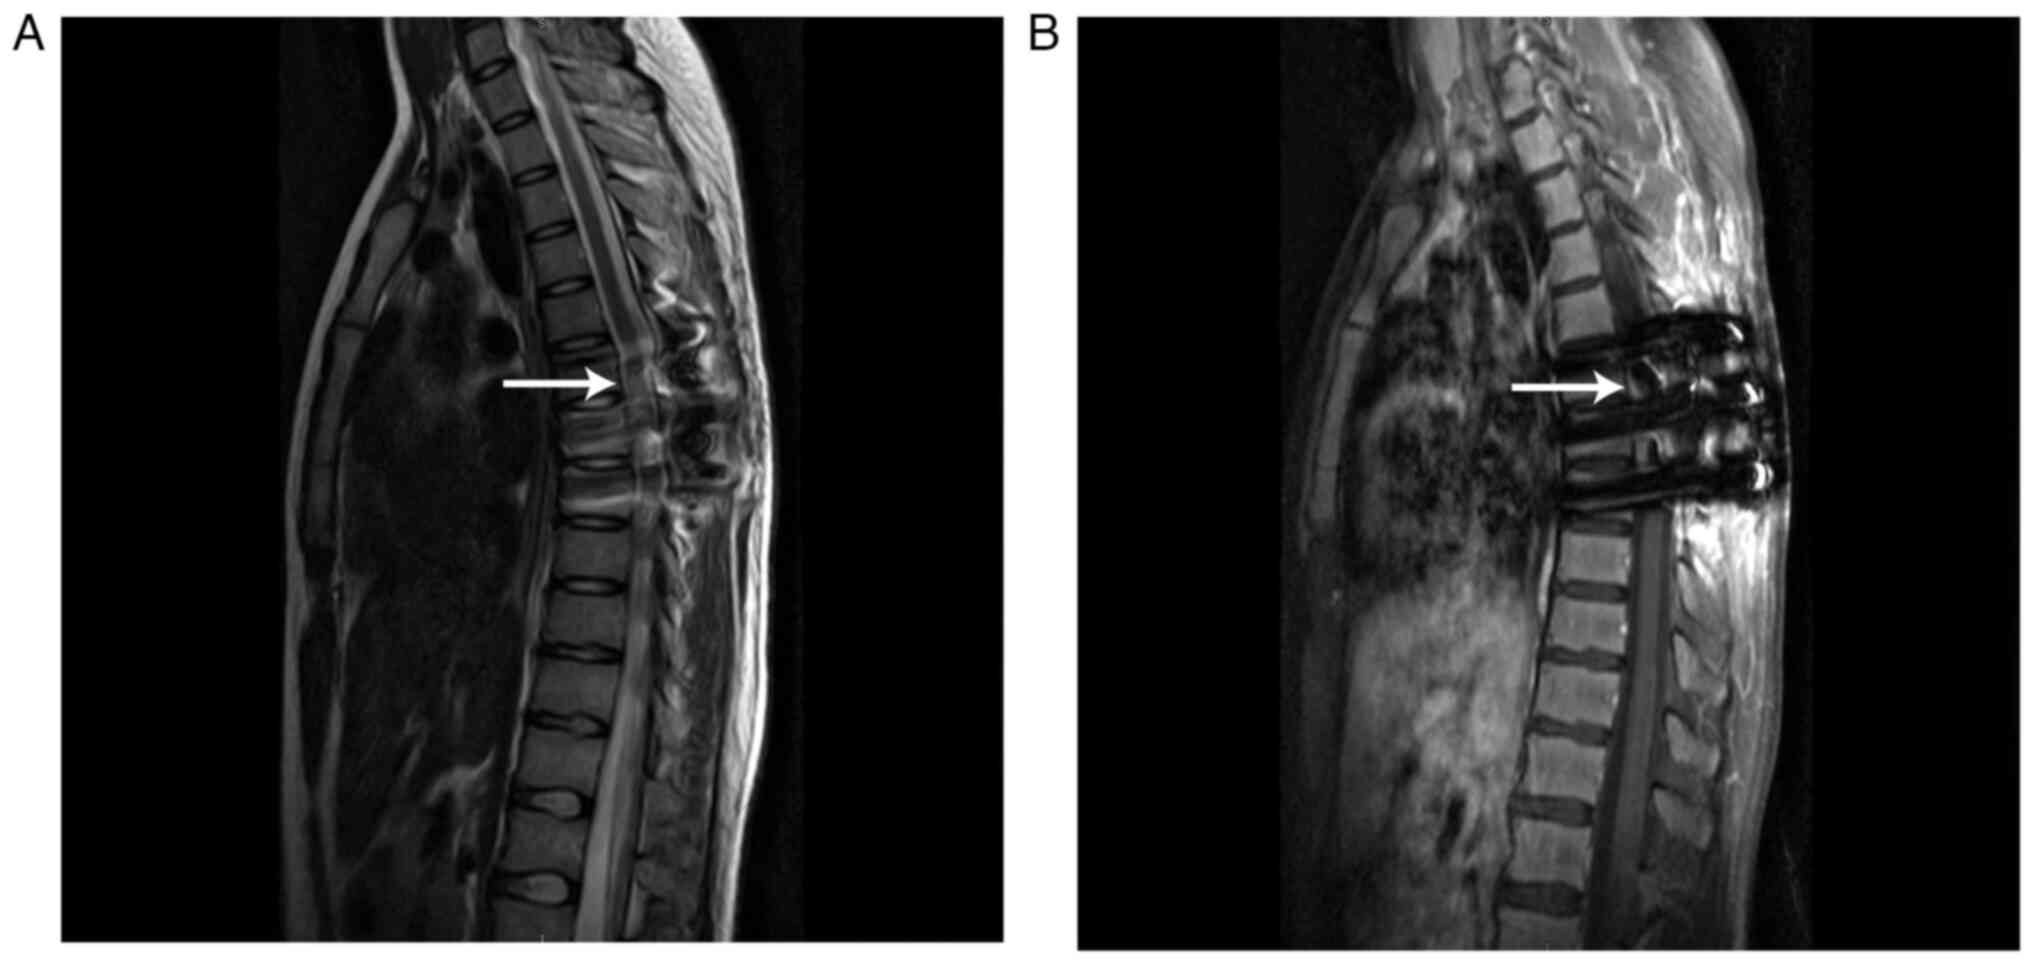

Due to the difficulty of intraspinal diagnostic biopsy and the possibility of tumor spread and metastasis, surgery to remove as much of the lesion as possible was considered the best option for the patient. The surgery was performed by orthopedic surgeons and neurosurgeons and the description of the operation in the present report was based on the operation records written by the surgeons. After imaging and hematology tests, the patient underwent thoracolumbar posterior focal lesion exploration and excisional biopsy, laminectomy and orthopedic internal fixation under general anesthesia. The tumor was located in both the epidural and subdural regions and appeared red and black because of the plentiful supply of blood. In addition, the tumor demonstrated aggressive and invasive growth and indistinct borders from the surrounding tissues. After piecemeal resection of the epidural tumor tissue, the subdural object was excised following cutting of the retrodural space of Okada and release of the cerebrospinal fluid (CSF). Postoperative MRI demonstrated a poorly defined, residual T2 hyperintense mass and a T1 isointense or hypointense mass in the T6-8 spinal canal, and the signal intensity demonstrated obvious enhancement in the lesion after contrast enhancement (Fig. 3).

Figure 3.

Postoperative MRI of a residual mass in the T6-8 spinal canal (white arrows). (A) T2-weighted image displaying the residual hyperintense mass. (B) T1-weighted image indicating the isointense or hypointense mass.